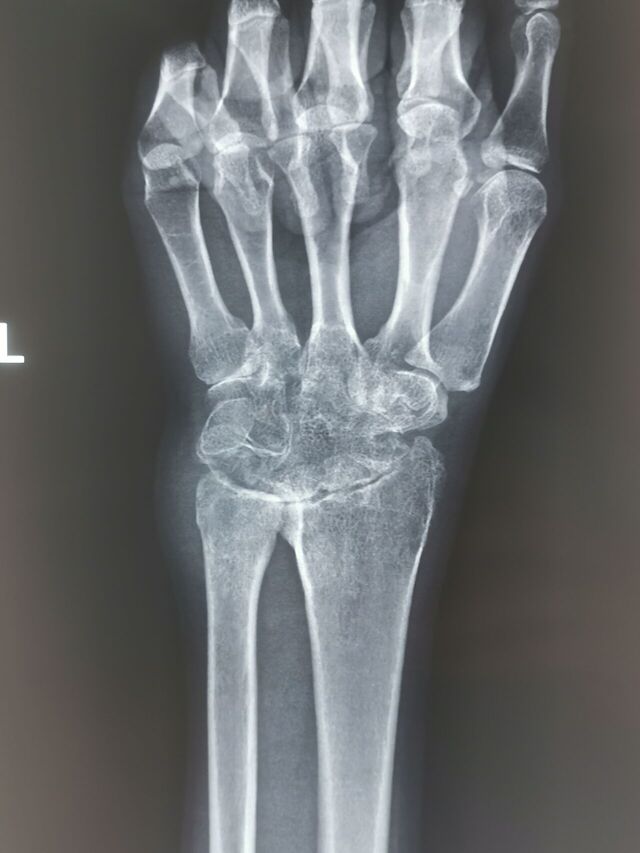

陈旧性月骨周围脱位,创伤性关节炎,下尺桡不稳

IMG_20231025_095800.jpg

IMG_20231025_095755.jpg

IMG_20231025_095748.jpg